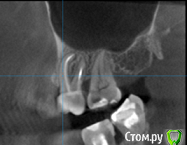

St. Опубликовано 26 августа, 2016 Поделиться Опубликовано 26 августа, 2016 Все три пролечены не очень хорошо, в идеале перелечить и сделать на них коронки. Но на сладкое ни один из них не может реагировать. Возможно реагирует 7 или 3, у которых оголена часть корней за счет вашего парадонтита. 1 Ссылка на комментарий

Гарриевич Опубликовано 27 августа, 2016 Поделиться Опубликовано 27 августа, 2016 возможно пропущенный канал, а возможно Вам "кажется" и реагируют все таки живые зубы. В любом случае данный снимок показывает не очень качественное лечение, но это только снимок 1 Ссылка на комментарий

татьяна tat Опубликовано 27 августа, 2016 Автор Поделиться Опубликовано 27 августа, 2016 возможно пропущенный канал, а возможно Вам "кажется" и реагируют все таки живые зубы. В любом случае данный снимок показывает не очень качественное лечение, но это только снимок Ссылка на комментарий

St. Опубликовано 27 августа, 2016 Поделиться Опубликовано 27 августа, 2016 Если кажется, что больше всего беспокоит 5, с него и начните. Но в будущем лучше перелечить все. 1 Ссылка на комментарий

Beznika Опубликовано 8 сентября, 2016 Поделиться Опубликовано 8 сентября, 2016 на 5 ке материал вывели за апекс. резекцию возможно придётся делать верхушки корня... + карман у вас есть за 6кой. а так всё равно перелечивать надо... масса пористая в каналах и не гомогенная. (не однородная) Ссылка на комментарий